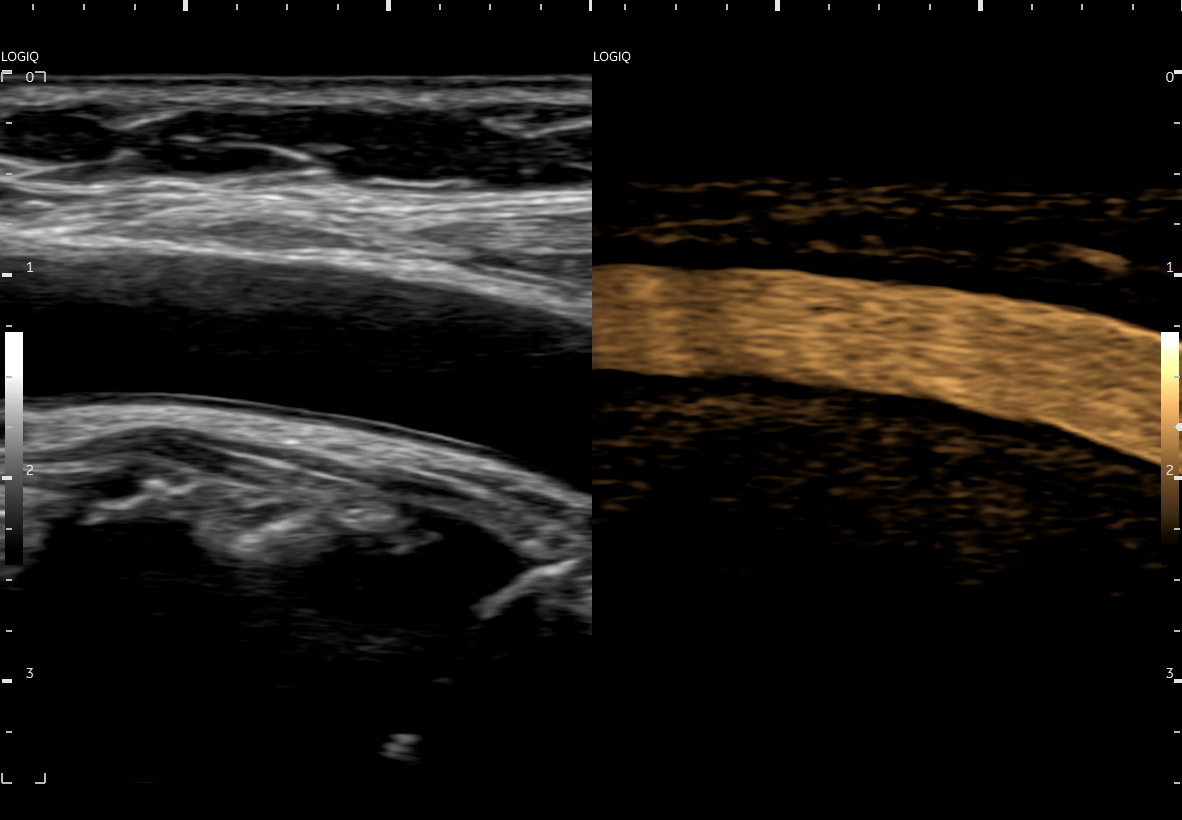

Tryb B-flow wyjątkowo korzystnie sprawdza się także przy badaniu wnętrza dużych i średnich naczyń. Otóż umożliwia on pewne zobrazowanie drożności naczynia, umożliwia wykazanie obecności / lokalizacji naczynia przy niesprzyjających warunkach obrazowania w trybie B, a poza tym uzyskiwane w omawianym trybie obrazy zarysów błony wewnętrznej naczyń (np. tętniczych blaszek miażdżycowych, skrzeplin przyściennych, zmian w przebiegu dysplazji włóknisto-mięśniowej, czy zapaleń tętnic) charakteryzują się wysoką rozdzielczością i kontrastowością. Skany dużych naczyń w trybie B-flow przypominają wręcz te uzyskiwane w klasycznej angiografii opartej o promieniowanie rentgenowskie. B-flow wykorzystywany może być praktycznie i rutynowo do obrazowania naczyń szyi i kończyn, naczyń wątroby, naczyń trzewnych, nerkowych oraz dużych naczyń brzusznych.